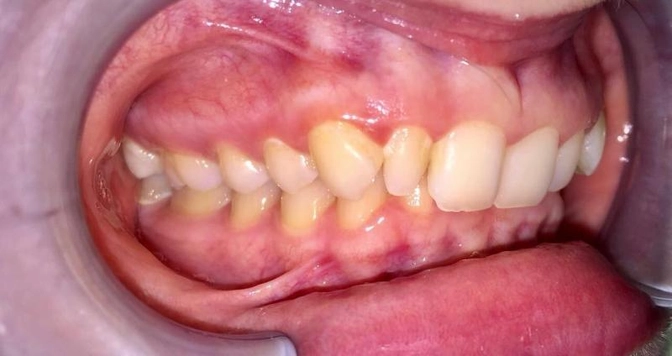

Называется такой прикус - глубокий.

Во время смыкания центральные зубы верхней челюсти перекрывают зубы нижней более, чем на 1/3.

Встречаются случаи полного перекрытия (как тут)

Верхняя челюсть словно крышка полностью перекрывает нижнюю.